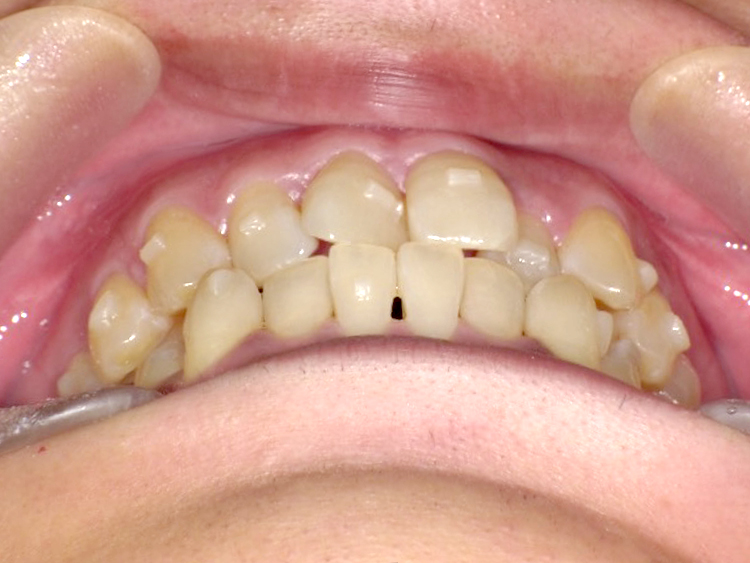

Before

After

| 主訴 | 上前歯のガタガタを治したい |

|---|---|

| 年齢 | --- |

| 治療 期間 |

約1年 |

| 治療 内容 |

インビザラインiGoで上顎のみ治療。 プチ矯正では前から3番目の歯は動かせないが、 この治療では動かすことができるので、 気になる箇所を綺麗に並べることができた。 |

| 治療費 | ¥352,000(税込)+月額調整料 |

| 治療のリスク | 歯と歯の間を削ることでスペースを確保するので、 場合によっては歯が染みる症状が出ることがある。 |